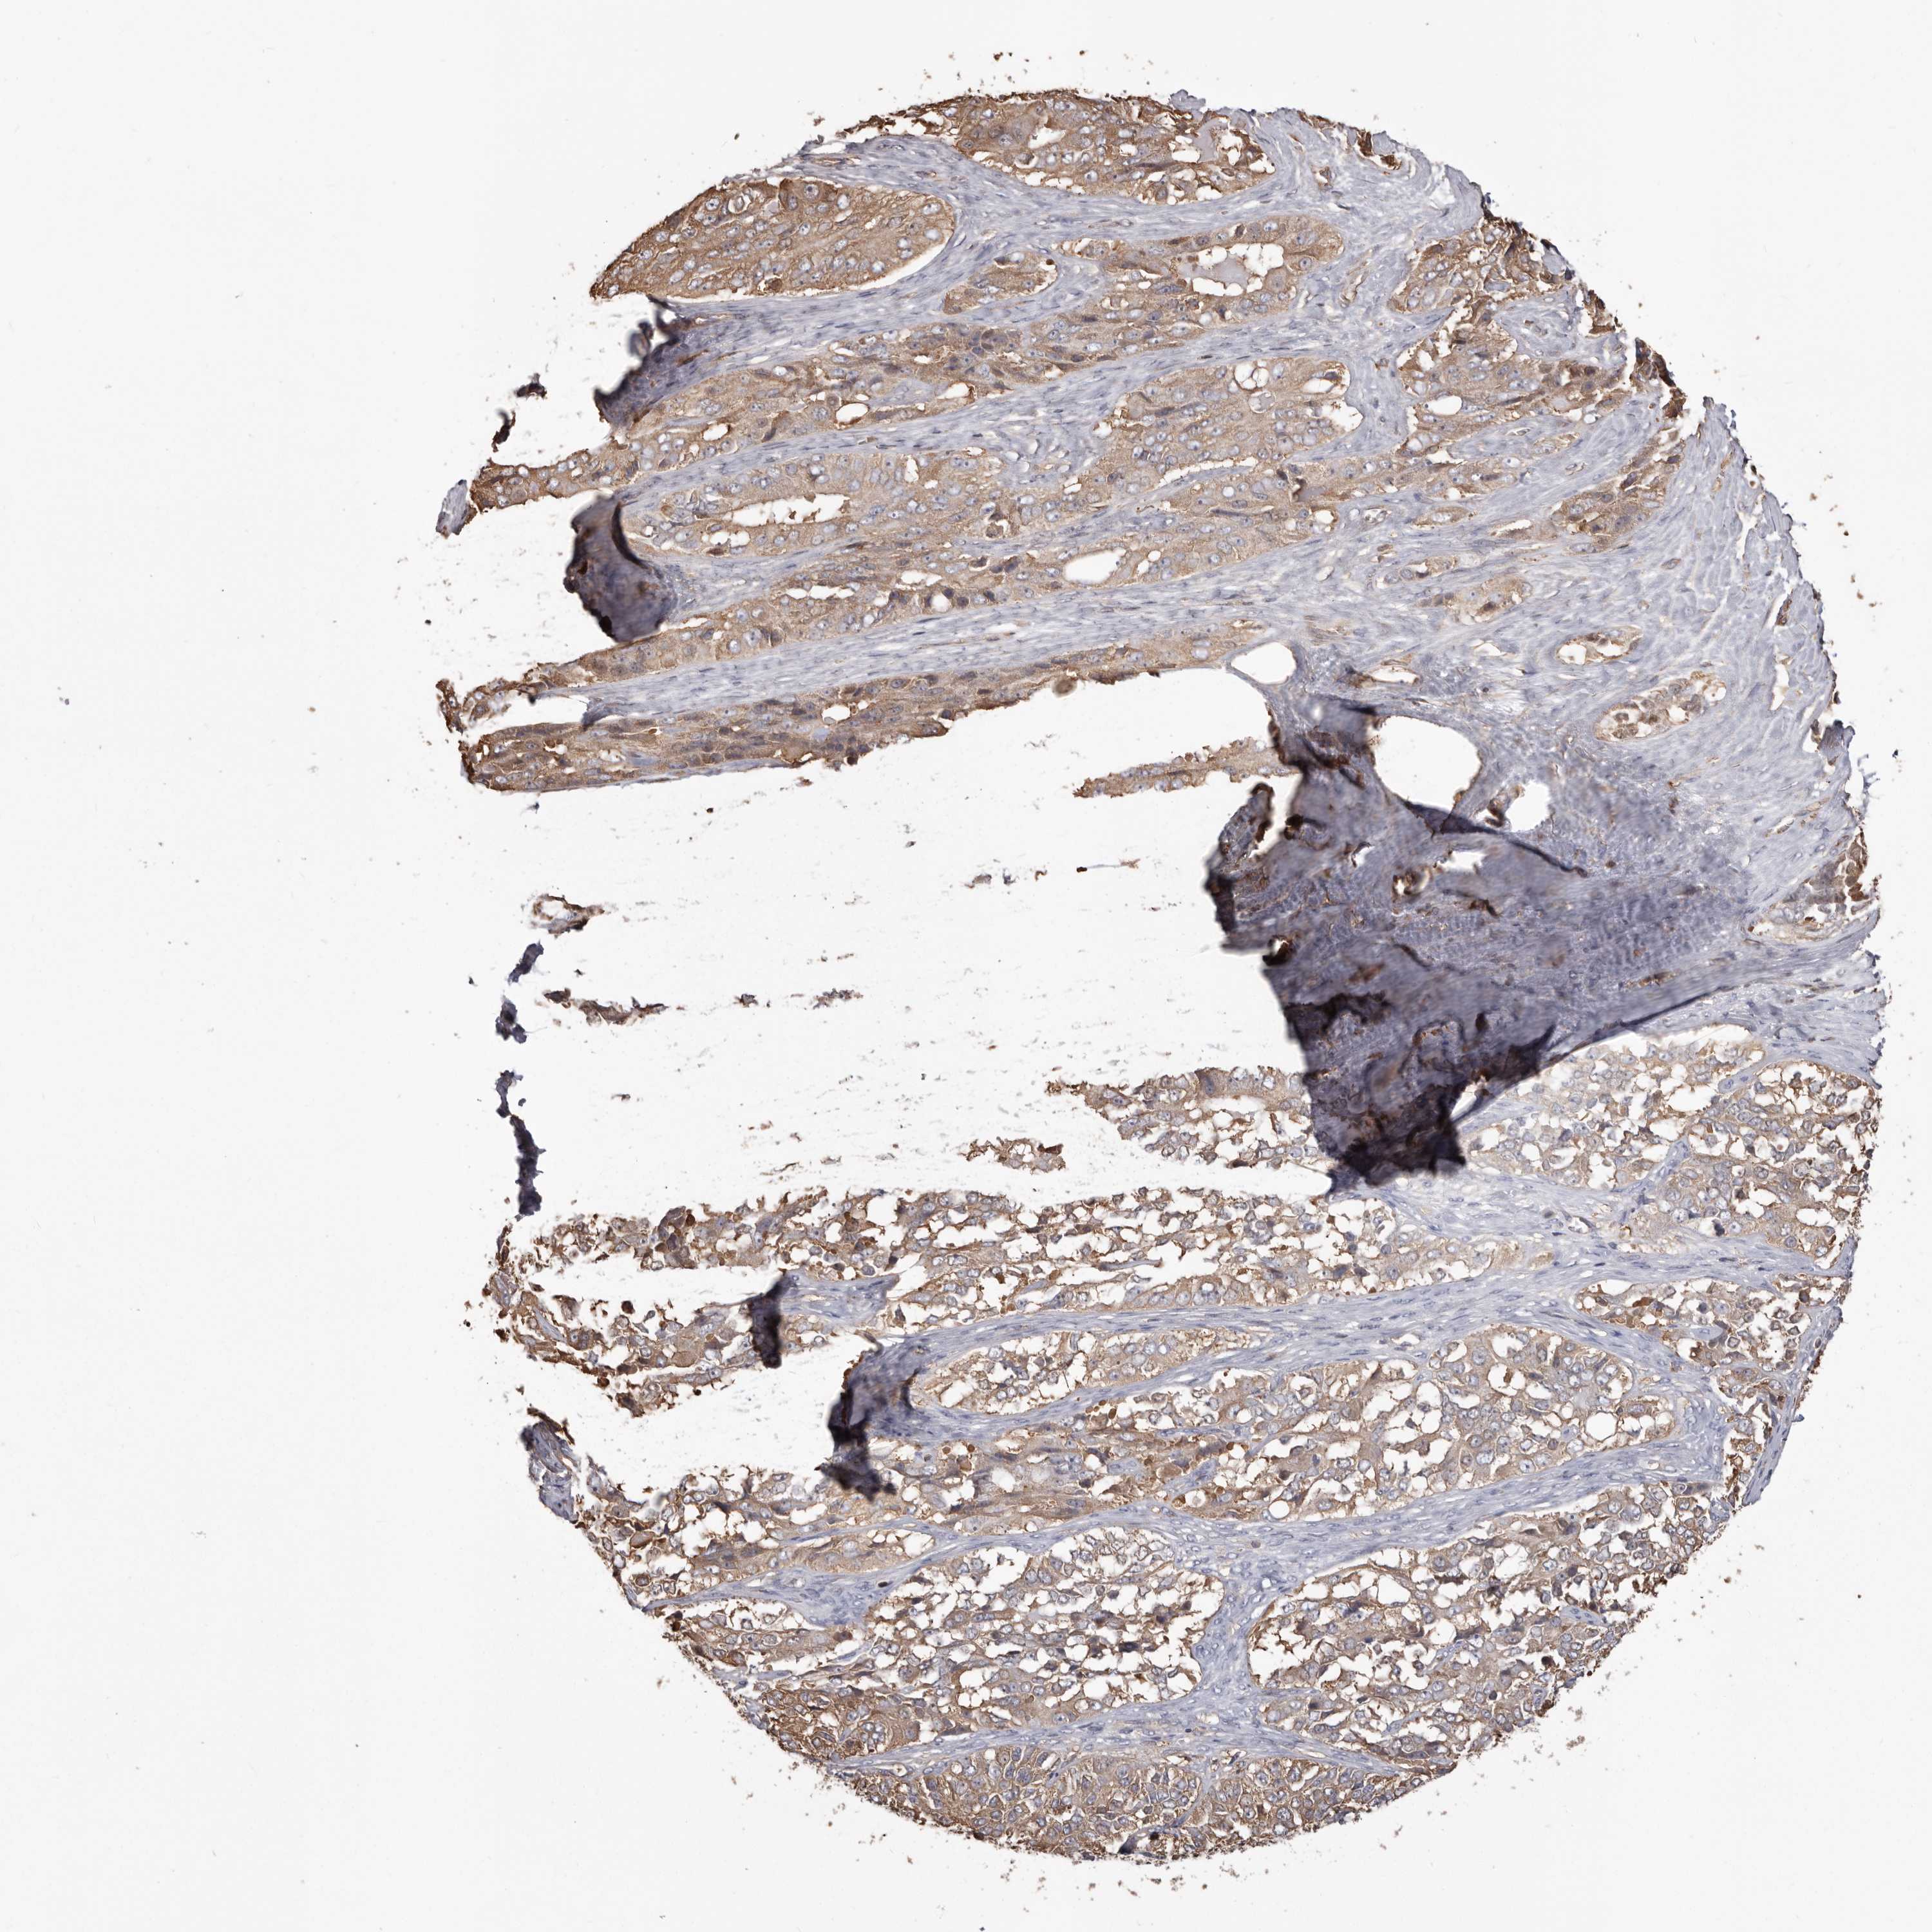

OVARIAN CANCER - Protein expressioni

A mouse-over function shows sample information and annotation data. Click on an image to view it in a full screen mode. Samples can be filtered based on level of antibody staining by selecting one or several of the following categories: high, medium, low and not detected. The assay and annotation is described here.

Note that samples used for immunohistochemistry by the Human Protein Atlas do not correspond to samples in the TCGA dataset.

Antibody stainingi

Antibody staining in the annotated cell types in the current human tissue is reported as not detected, low, medium, or high, based on conventional immunohistochemistry profiling in selected tissues. This score is based on the combination of the staining intensity and fraction of stained cells.

Each image is clickable and will lead to virtual microscopy that enables deeper exploration of all samples and also displays staining intensity scores, fraction scores and subcellular localization as well as patient and tissue information for each sample.

Antibody HPA029501

Antibody CAB019421

Staining

High

Medium

Low

Not detected

Intensity

Strong

Moderate

Weak

Negative

Quantity

>75%

75%-25%

<25%

None

Location

Nuclear

Cytoplasmic/membranous

Cytoplasmic/membranous,nuclear

Cystadenocarcinoma, serous, NOS